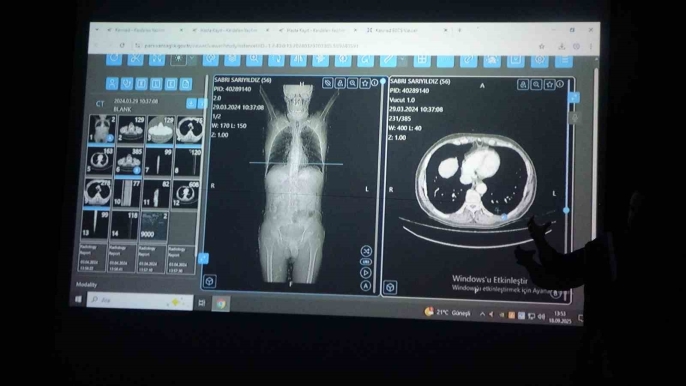

Erciş ilçesinde yaşayan 56 yaşındaki Sabri Sarıyıldız'ın tedavisinde yapay zekâ destekli yazılımın önerdiği tedavi planı uygulandı. Başarılı bir cerrahi operasyon sonrası Sarıyıldız sağlığına kavuştu. Van Bölge Eğitim ve Araştırma Hastanesi Genel Cerrahi Uzmanı Prof. Dr. Sebahattin Çelik, yapay zekânın sağlık alanında giderek yaygınlaştığını ve bu teknolojinin hastalara doğru tedaviyi sunmak için kullanıldığını vurguladı. Çalışmanın dünyada bir ilk olduğunu da sözlerine ekledi. Sarıyıldız ise, tedavi süreci ve başarılı operasyon hakkında olumlu değerlendirmelerde bulundu.